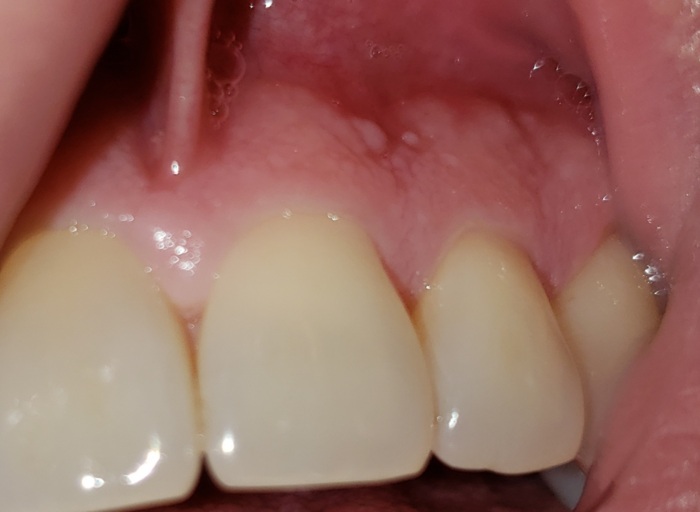

White stuff appearing in mouth?

Recently brushing my teeth, eating and drinking water has been leaving a stinging sensation in my mouth. Particularly around my gums sometimes but mostly on the floor of my mouth. I had a look and found these white stuff on the floor of my mouth. What is it?

From the picture, it appears you may be having an allergic reaction to whatever you are eating or possibly your toothpaste or mouthwash. Try to eliminate citrus and spicy food from your diet temporarily. If you recently switched your mouthwash or toothpaste, try and revert to your previous brand. Personally, I cannot use Crest Prohealth products, it causes my tissue to become white and slough off. Highly acidic foods such as citrus and spicy foods can irritate the tissues as well. The more bland your diet the better, temporarily while the areas heal.